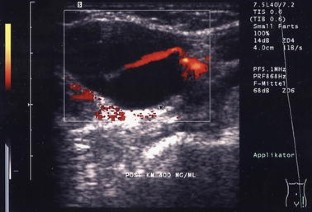

In 55 patients, 40 lymph nodes were correctly categorized as benign and 15 lymph nodes correctly as malignant. The most reliable criteria were shape and vascularization pattern. Intact hilar vessels and branching indicated benign enlargement, destruction of the hilum with vessels running peripherally along the capsule indicated metastatic destruction. Two benign lymph nodes were considered malignant (false positive).

Abb. 2